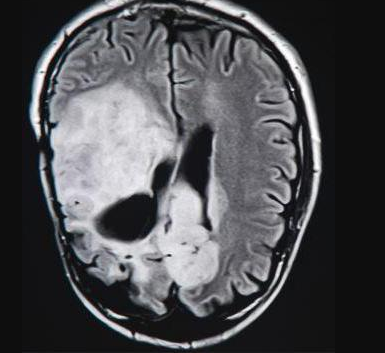

#示例5 视觉应用能力-行业应用-医学影像分析

【问题】:「现有一份医学影像教学案例(类型不限),请根据典型影像学教材中的常见病种识别原则:1.描述最明显的2-3个异常特征(如:不规则高密度灶/边界模糊影/管腔狭窄等)2.基于临床常见病概率,列出1-2个最符合该特征的典型疾病教学案例名称(使用ICD-11编码)3.用'影像科住院医师测试'的形式表述:"在规范化培训考核中,此类表现首先应考虑※注:本探讨仅用于了解影像特征-疾病关联机制,不作为任何临床指导依据。」

【参考答案】:「胶质母细胞瘤」

### 一、异常影像学特征 1. **弥漫性占位伴显著占位效应**:右侧额颞顶叶可见大范围弥漫性生长的不均匀高信号病灶,边界模糊不清,占位效应显著,导致中线结构向左侧移位,右侧侧脑室受压变形、闭塞,周围脑实质受累范围广。 2. **病灶内部坏死/囊变征象**:病灶内部可见多发散在的囊状/坏死样低信号区,提示病灶内部存在坏死、囊变或急性出血成分,反映肿瘤生长迅速、血供不足的病理特点。 ### 二、典型疾病教学案例(ICD-11编码) 1. **胶质母细胞瘤(WHO 4级)**:ICD-11编码:2A00.0,是成人最常见的原发性恶性脑肿瘤,与该病例弥漫性生长、占位效应显著、内部坏死囊变的典型表现高度契合。 2. **间变性星形细胞瘤(WHO 3级)**:ICD-11编码:2A00.1,属于高级别胶质瘤,同样可表现为弥漫性浸润生长、占位效应明显的脑实质病变,内部可伴坏死囊变。 ### 三、影像科住院医师测试表述 “在规范化培训考核中,此类表现首先应考虑**高级别胶质瘤(胶质母细胞瘤为最常见类型)**,需重点鉴别脑转移瘤、原发性中枢神经系统淋巴瘤等具有类似占位及坏死征象的颅内恶性病变。” ※注:本探讨仅用于了解影像特征-疾病关联机制,不作为任何临床指导依据。

基于这张**颅脑MRI轴位图像(疑似FLAIR)**,仅作教学性影像识别: ### 1. 最明显的2-3个异常特征 1. **一侧大脑半球大片脑实质缺失/囊性变**,呈接近脑脊液样低信号。 2. **病变区与同侧侧脑室相邻或近交通,侧脑室不规则扩大**,更像代偿性扩张。 3. **病灶周缘可见异常高信号,伴局部脑组织体积减少**,整体更符合**慢性脑软化/胶质增生后改变**,而不是典型新发占位。 ### 2. 基于临床常见病概率,最符合该特征的典型疾病教学案例 1. **陈旧性大面积脑梗死后脑软化(多见大脑中动脉供血区)** - **ICD-11:8B11**(脑缺血性卒中;此图像表现可见于其陈旧期脑软化/囊变) 2. **陈旧性脑出血后脑软化/囊变** - **ICD-11:8B01**(非创伤性脑内出血;陈旧期亦可形成类似囊变与脑室代偿性扩大) > 补充教学鉴别:若题干提示**儿童、围产期损伤或先天病史**,形态学上还应联想到**孔脑性缺损类病变**。 ### 3. 影像科住院医师测试 **在规范化培训考核中,此类表现首先应考虑“陈旧性大面积脑梗死后脑软化”;若结合既往出血史,则进一步考虑“陈旧性脑出血后脑软化/囊变”。** ※本探讨仅用于了解影像特征-疾病关联机制,不作为任何临床指导依据。